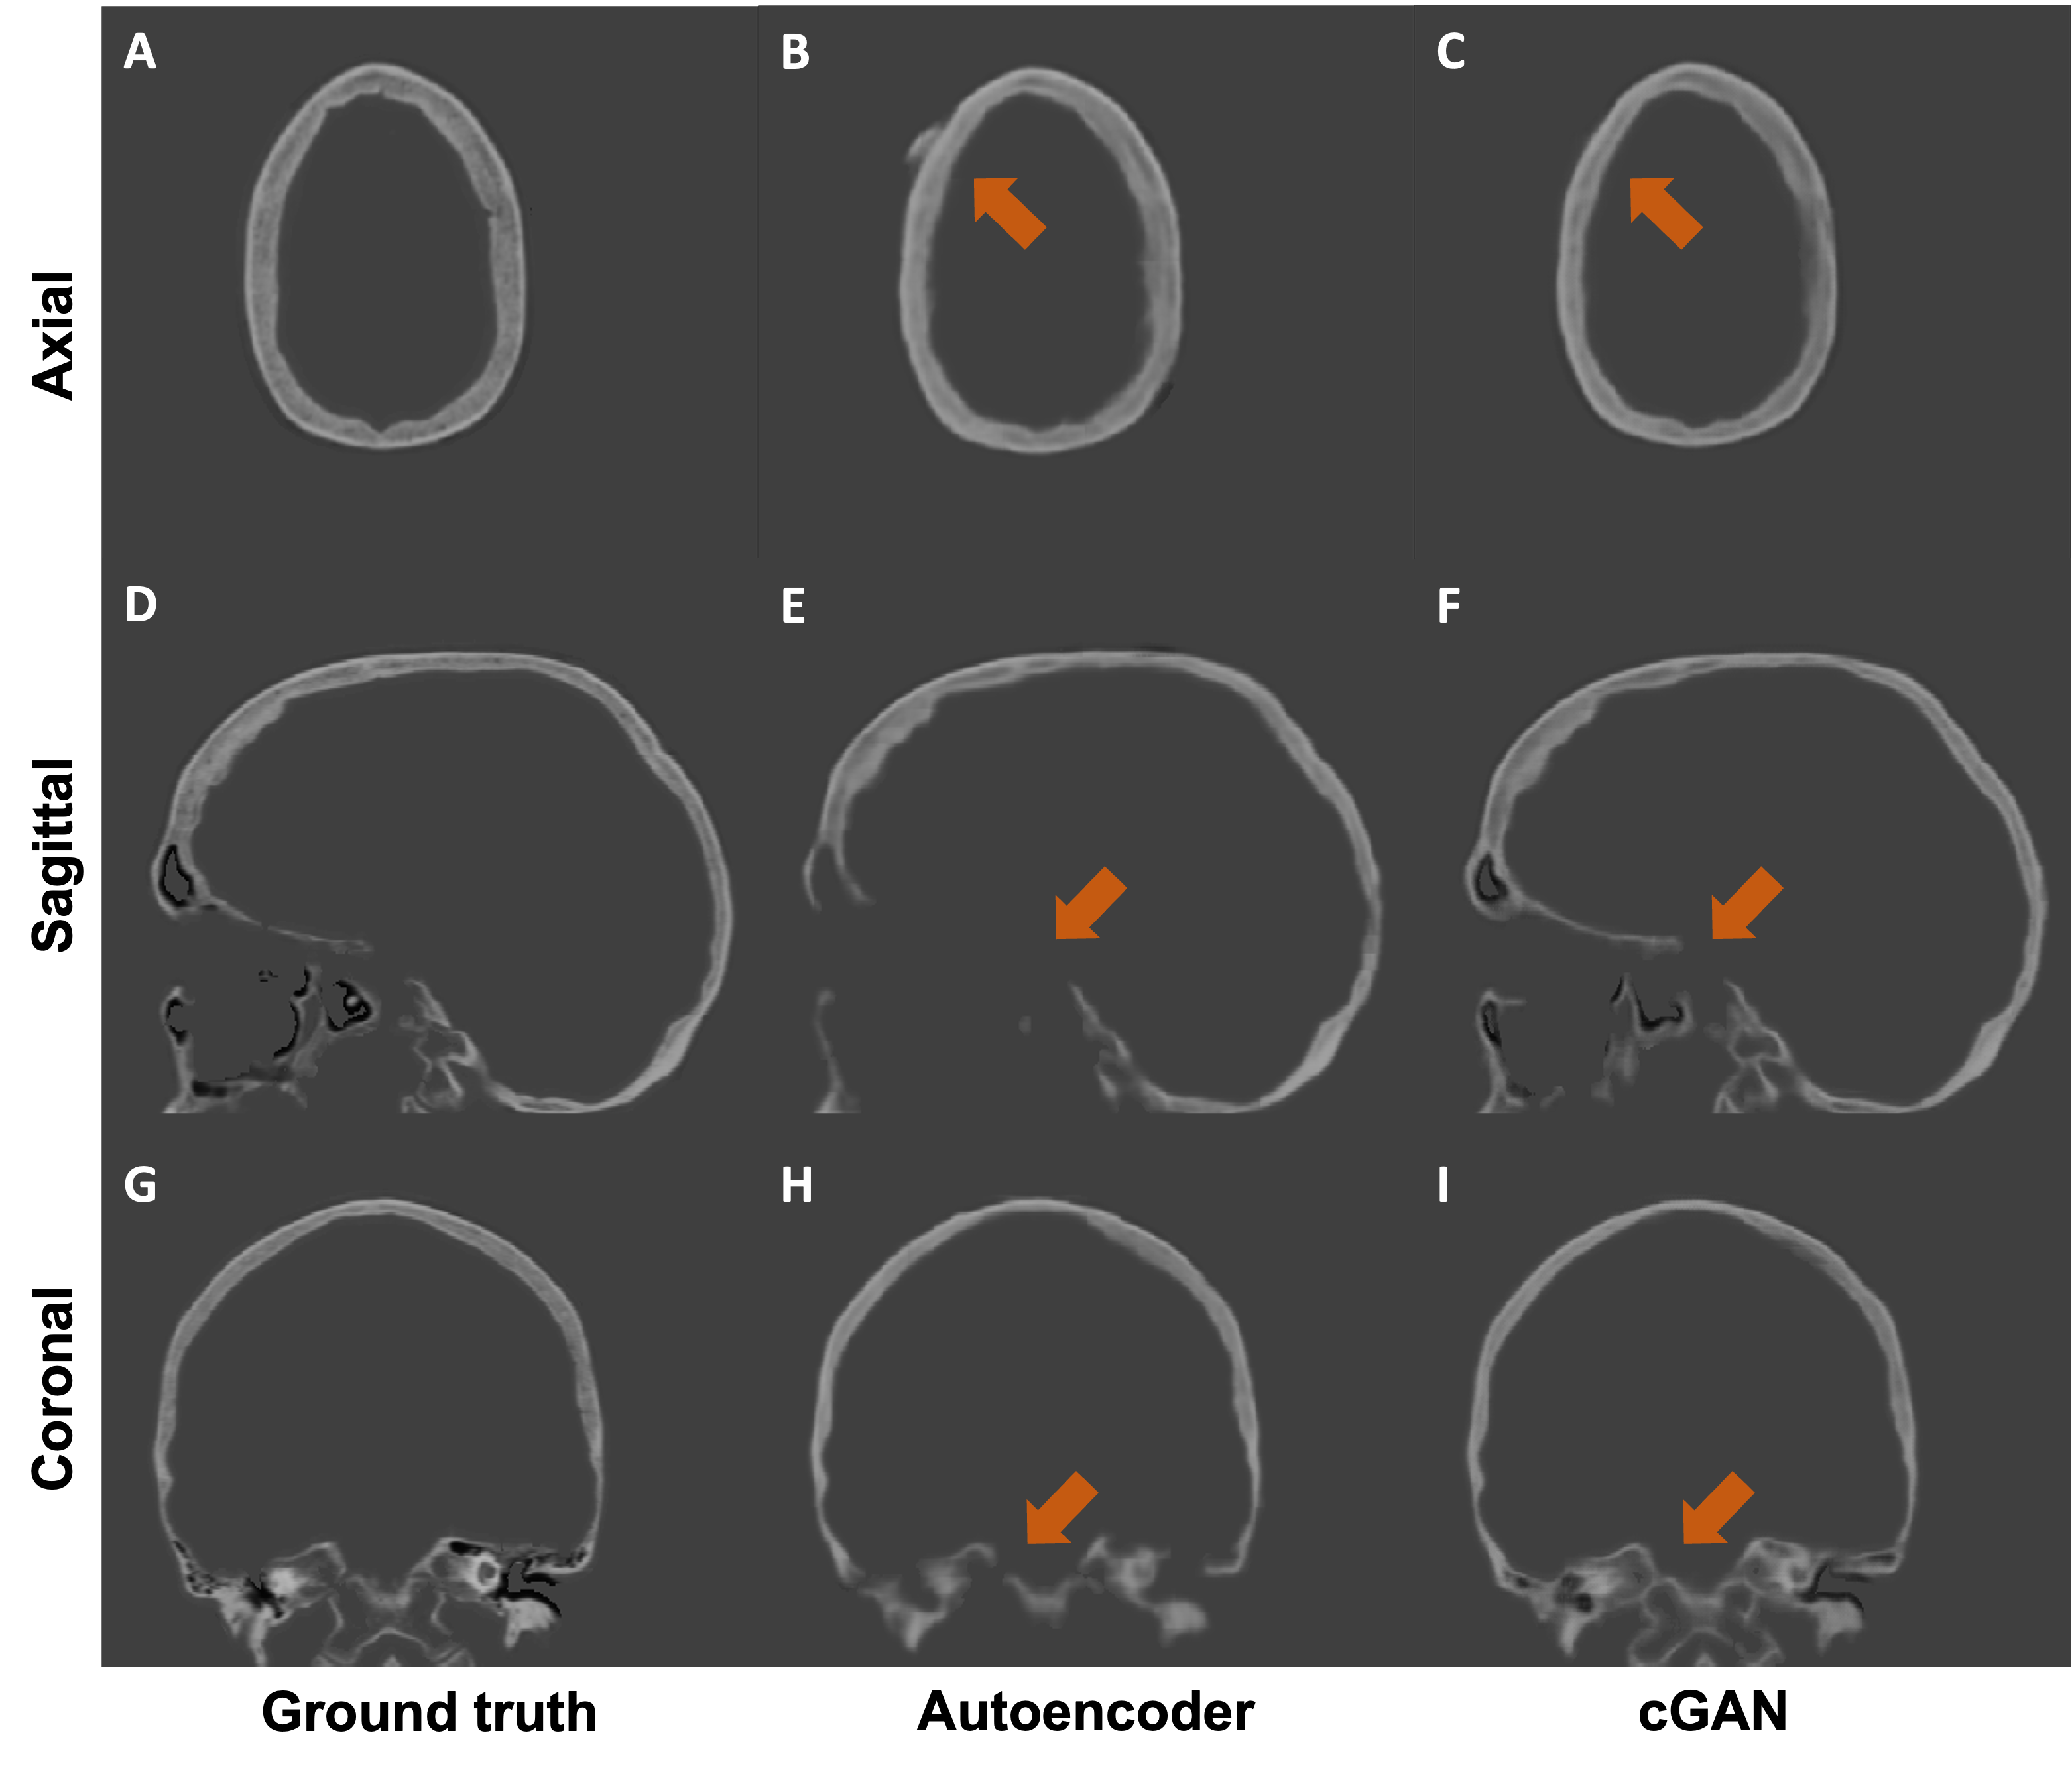

Refer to caption

Figure 2: Qualitative results of an example case from the testing set. We compare the two mainstream MR-CT translation methods: autoencoder (middle column) and our cGAN (right column). The major differences between two approaches are highlighted by orange arrows.

We performed both quantitative and qualitative evaluations of image similarity on our testing set. Quantitatively, we showed the box and whisker plot in Fig 1. Specifically, the MAEs between rCTs and sCTs in skull regions were 192.31±28.21plus-or-minus192.3128.21192.31\pm 28.21 HU and 206.83±27.91plus-or-minus206.8327.91206.83\pm 27.91 for cGAN and autoencoder, respectively. We performed paired t-test and found that the difference in mean MAE was statistically significant (p-value <0.01absent0.01<0.01). Qualitatively, as shown in Fig 2, we found that at the inferior part of the skull, the synthesized skull exhibited larger difference than at the superior part. The synthetic skull generated by cGAN also included more details and had sharper appearances compared to the one generated by autoencoder. Lastly, we note that our synthesized skulls were spatially continuous in all views and highly comparable to real skulls, as shown in Fig 3.